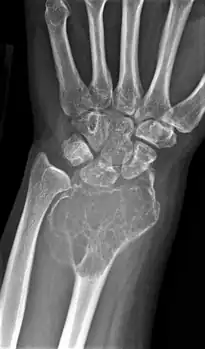

| X-ray of a giant-cell bone tumor in the head of the fourth metacarpal of the left hand | |

On X-ray, giant-cell tumors (GCTs) are lytic/lucent lesions that have an epiphyseal location and grow to the articular surface of the involved bone.[11] Radiologically the tumors may show characteristic 'soap bubble' appearance.[12] They are distinguishable from other bony tumors in that GCTs usually have a nonsclerotic and sharply defined border. About 5% of giant-cell tumors metastasize, usually to a lung, which may be benign metastasis,[13] when the diagnosis of giant-cell tumor is suspected, a chest X-ray or computed tomography may be needed. MRI can be used to assess intramedullary and soft tissue extension.